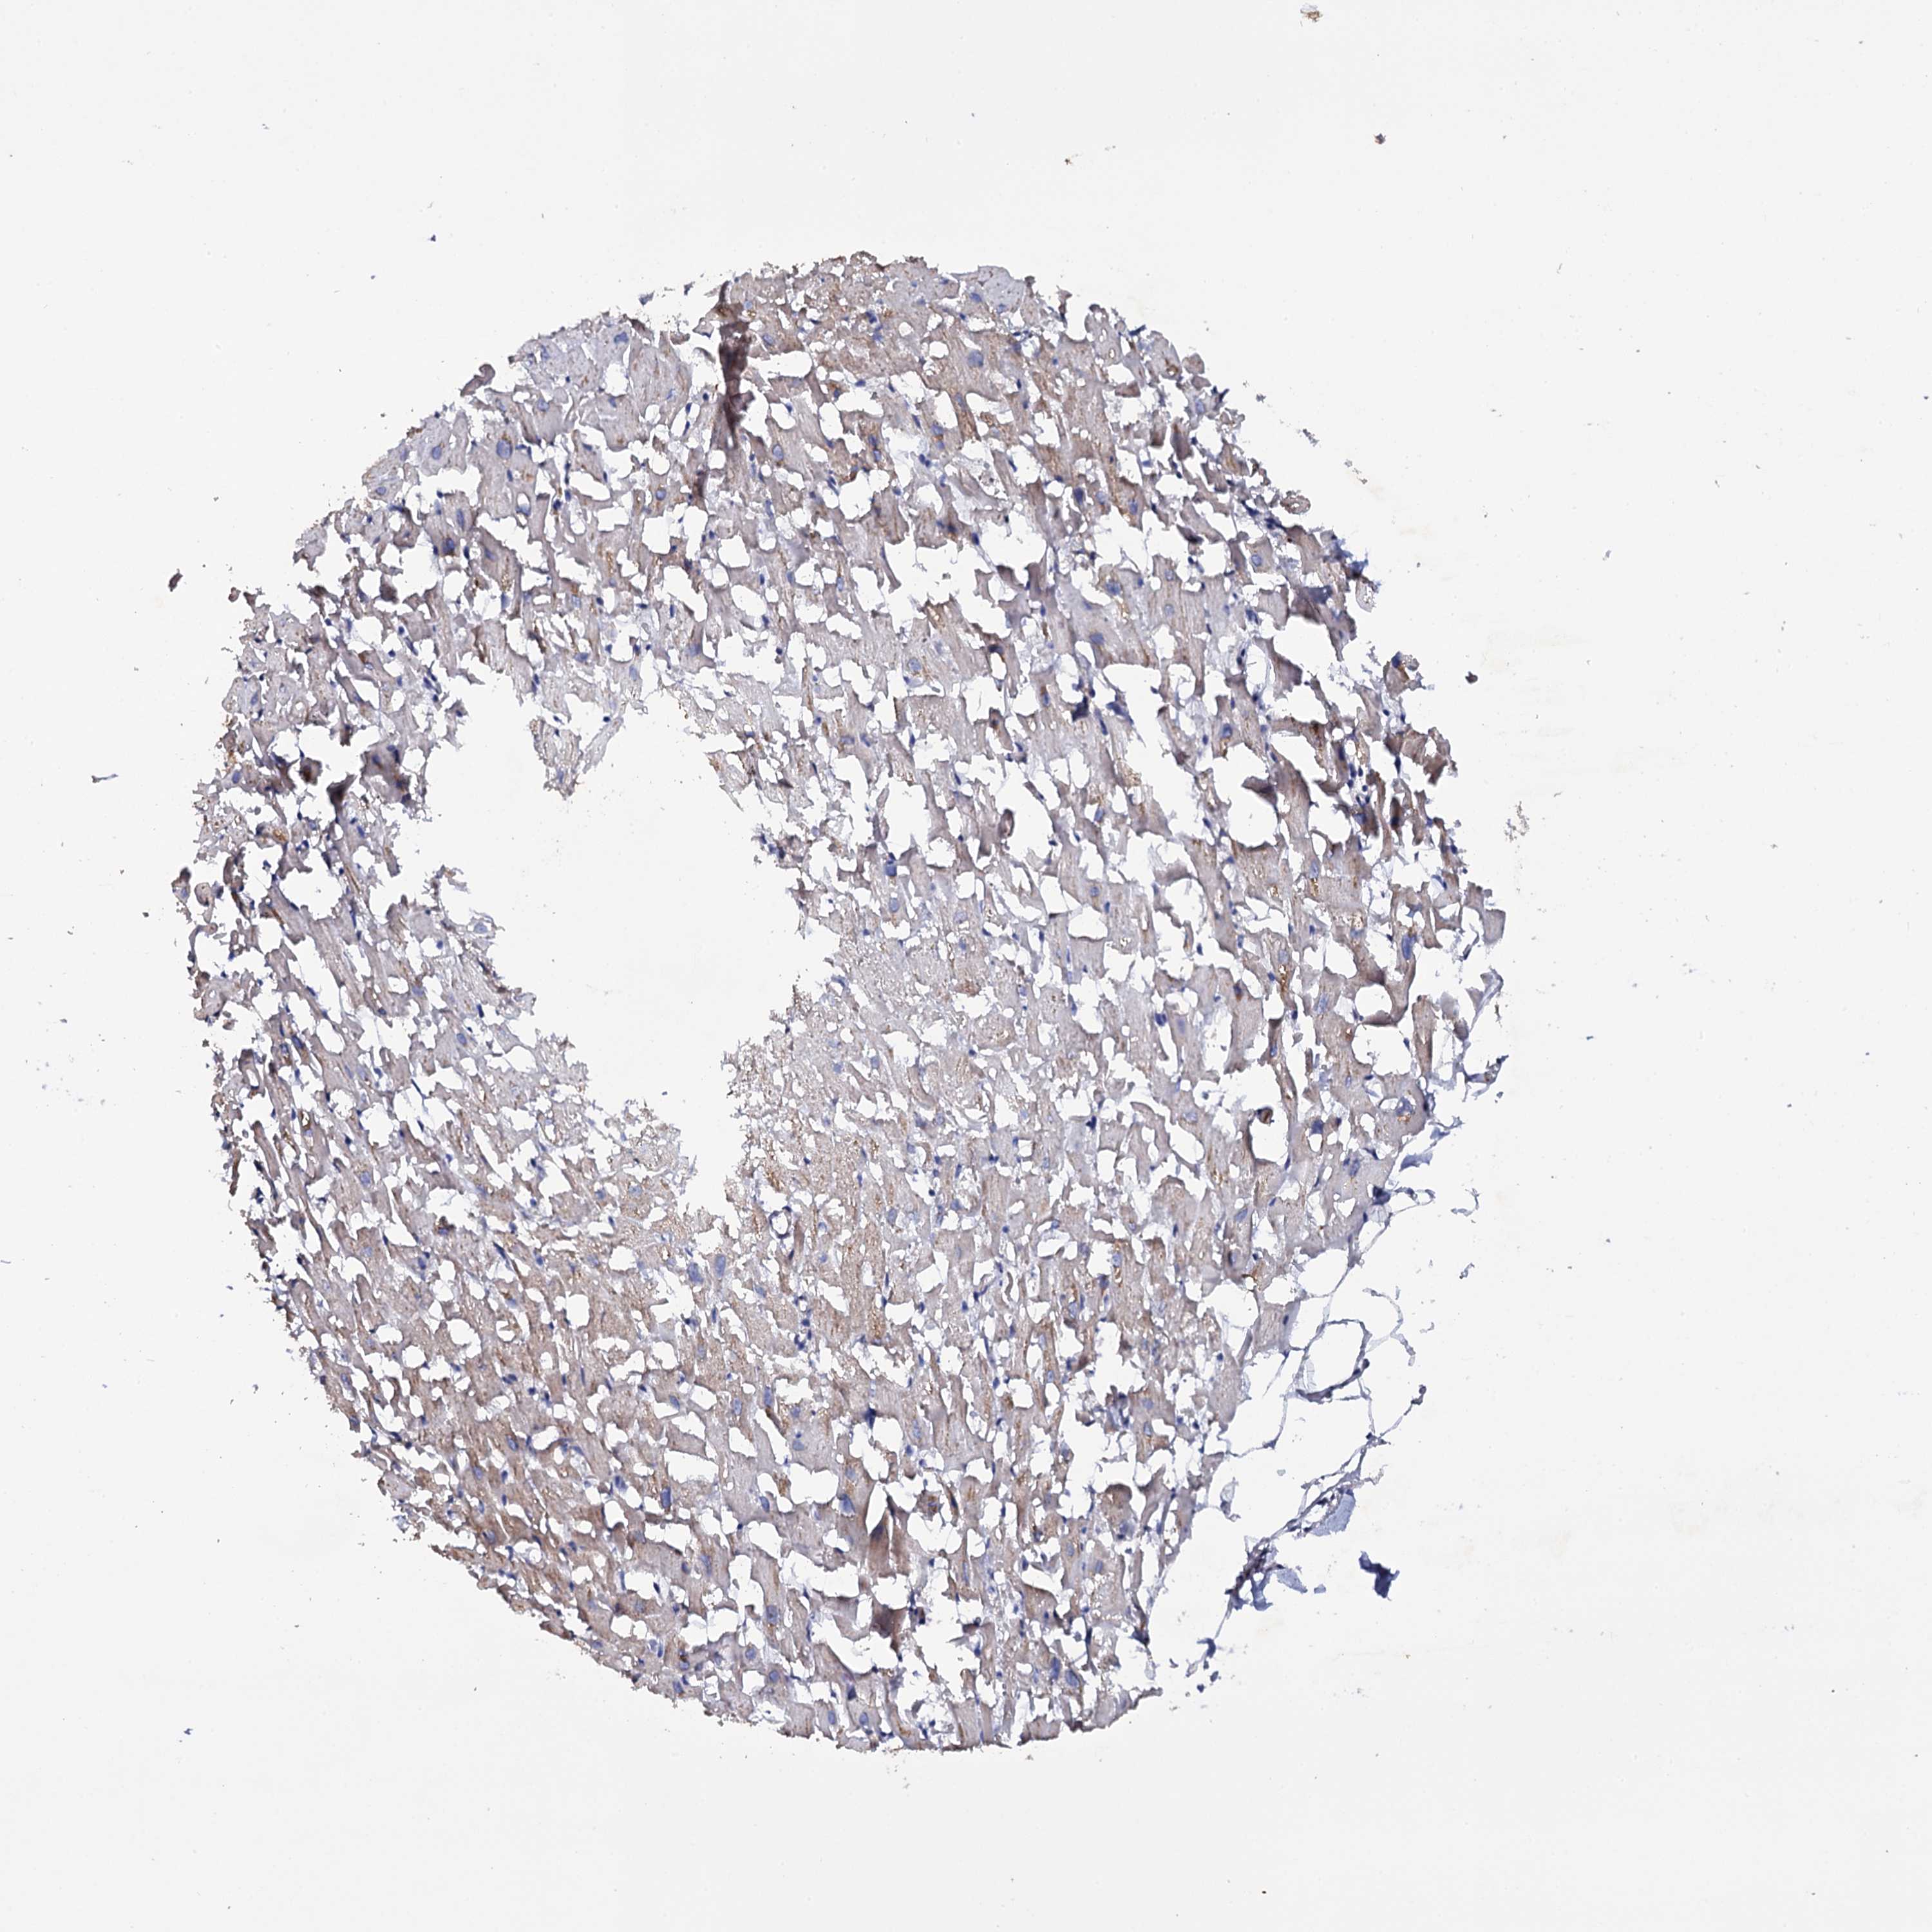

HEART MUSCLE - Antibody stainingi

Antibody staining in the annotated cell types in the current human tissue is reported as not detected, low, medium, or high, based on conventional immunohistochemistry profiling in selected tissues. This score is based on the combination of the staining intensity and fraction of stained cells.

Each image is clickable and will lead to virtual microscopy that enables deeper exploration of all samples and also displays staining intensity scores, fraction scores and subcellular localization as well as patient and tissue information for each sample.

Antibody HPA040403Antibody HPA058848

Cardiomyocytes LowNot detected